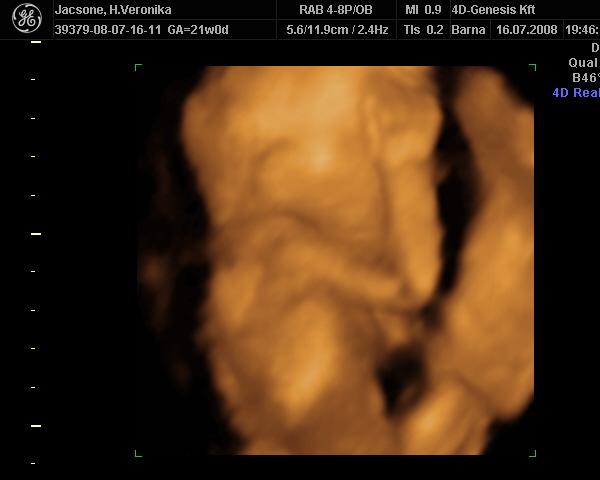

Mi jól vagyunk kedden voltam dokinál minden oké a kisfiammal.Már 75mm a buksilya és kb 1400gramm(vasgyúró)Zsófi ennyi idösen 69mm fejecskével és kb 1100gramm volt :lol: majd rakok képet csak késön szóltam és a tv-ről fényképeztem mert már elkapcsolt a doki :cry: Zsófi vasárnap lesz 2éves már úgy várom tőlünk Ponyt meg egy kisruhát kap anyuméktól meg babát olyan kiváncsi vagyok mit szól majd :lol: :lol: Kép Kép